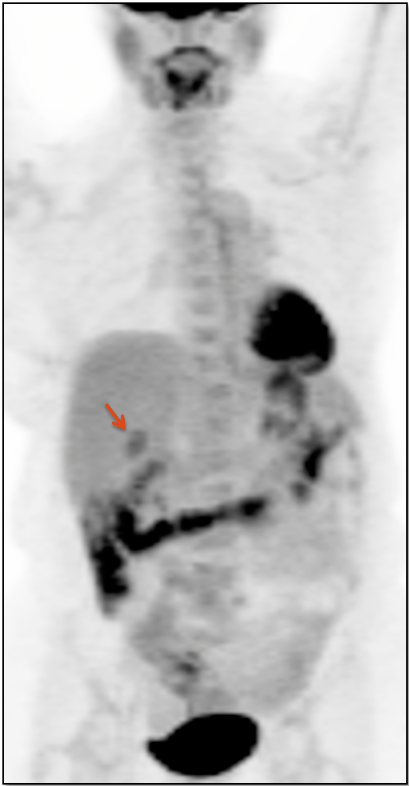

- Maximum Intensity Projection (MIP)

- 3-D Rotating MIP & Coronal “Quick MIP”